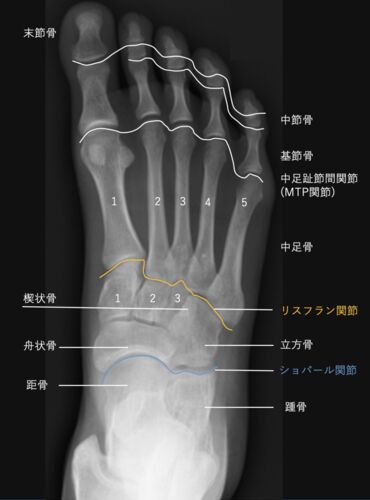

足部レントゲン写真のみかた

【構造】 【単純X線写真】 −正面像 −側面写真 −斜位像 【構造】 ・足部は26個の骨で構成され,踵骨,距骨で構成される後足部,舟状骨,立方骨,楔状骨群で構成される中足部,中足骨,趾骨で構成される前足部に分類される. ・後足部と中足部をつなぐChopart…